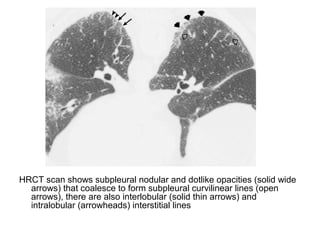

HRCT scan shows subpleural nodular and dotlike opacities (solid wide

arrows) that coalesce to form subpleural curvilinear lines (open

arrows), there are also interlobular (solid thin arrows) and

intralobular (arrowheads) interstitial lines